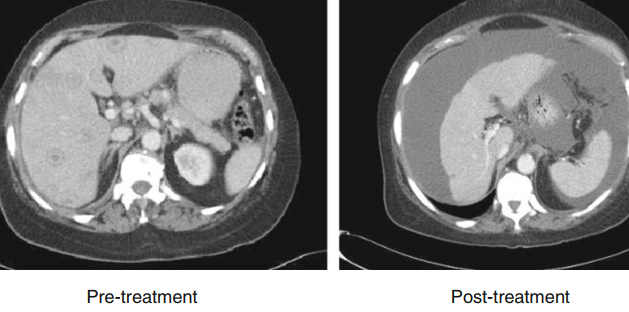

乳腺癌肝转移,化疗前可见肝内多发转移灶,化疗结束后可见肝体积缩小,肝包膜凹陷,类似于肝硬化。